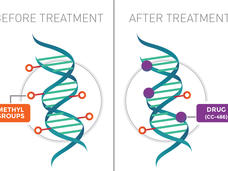

Maintenance Therapy with CC-486 Extends Survival of Adults with AML

Maintenance therapy with CC-486 extended overall survival of adults with the blood cancer acute myeloid leukemia (AML) in a large clinical trial. CC-486 is a pill form of another cancer therapy called azacitidine (Vidaza).